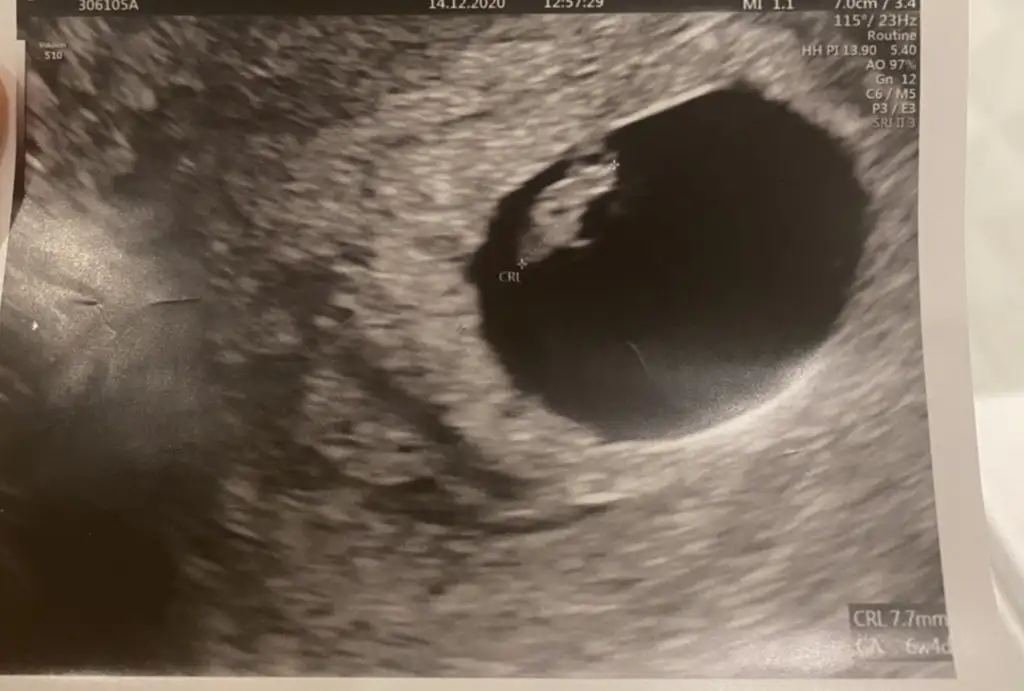

Ayrıca bir DR yani bilim adamı teorisi olan Ramzi teorisi ile bebek cinsiyeti ultrason görüntüsü ile tahmin edilebilir